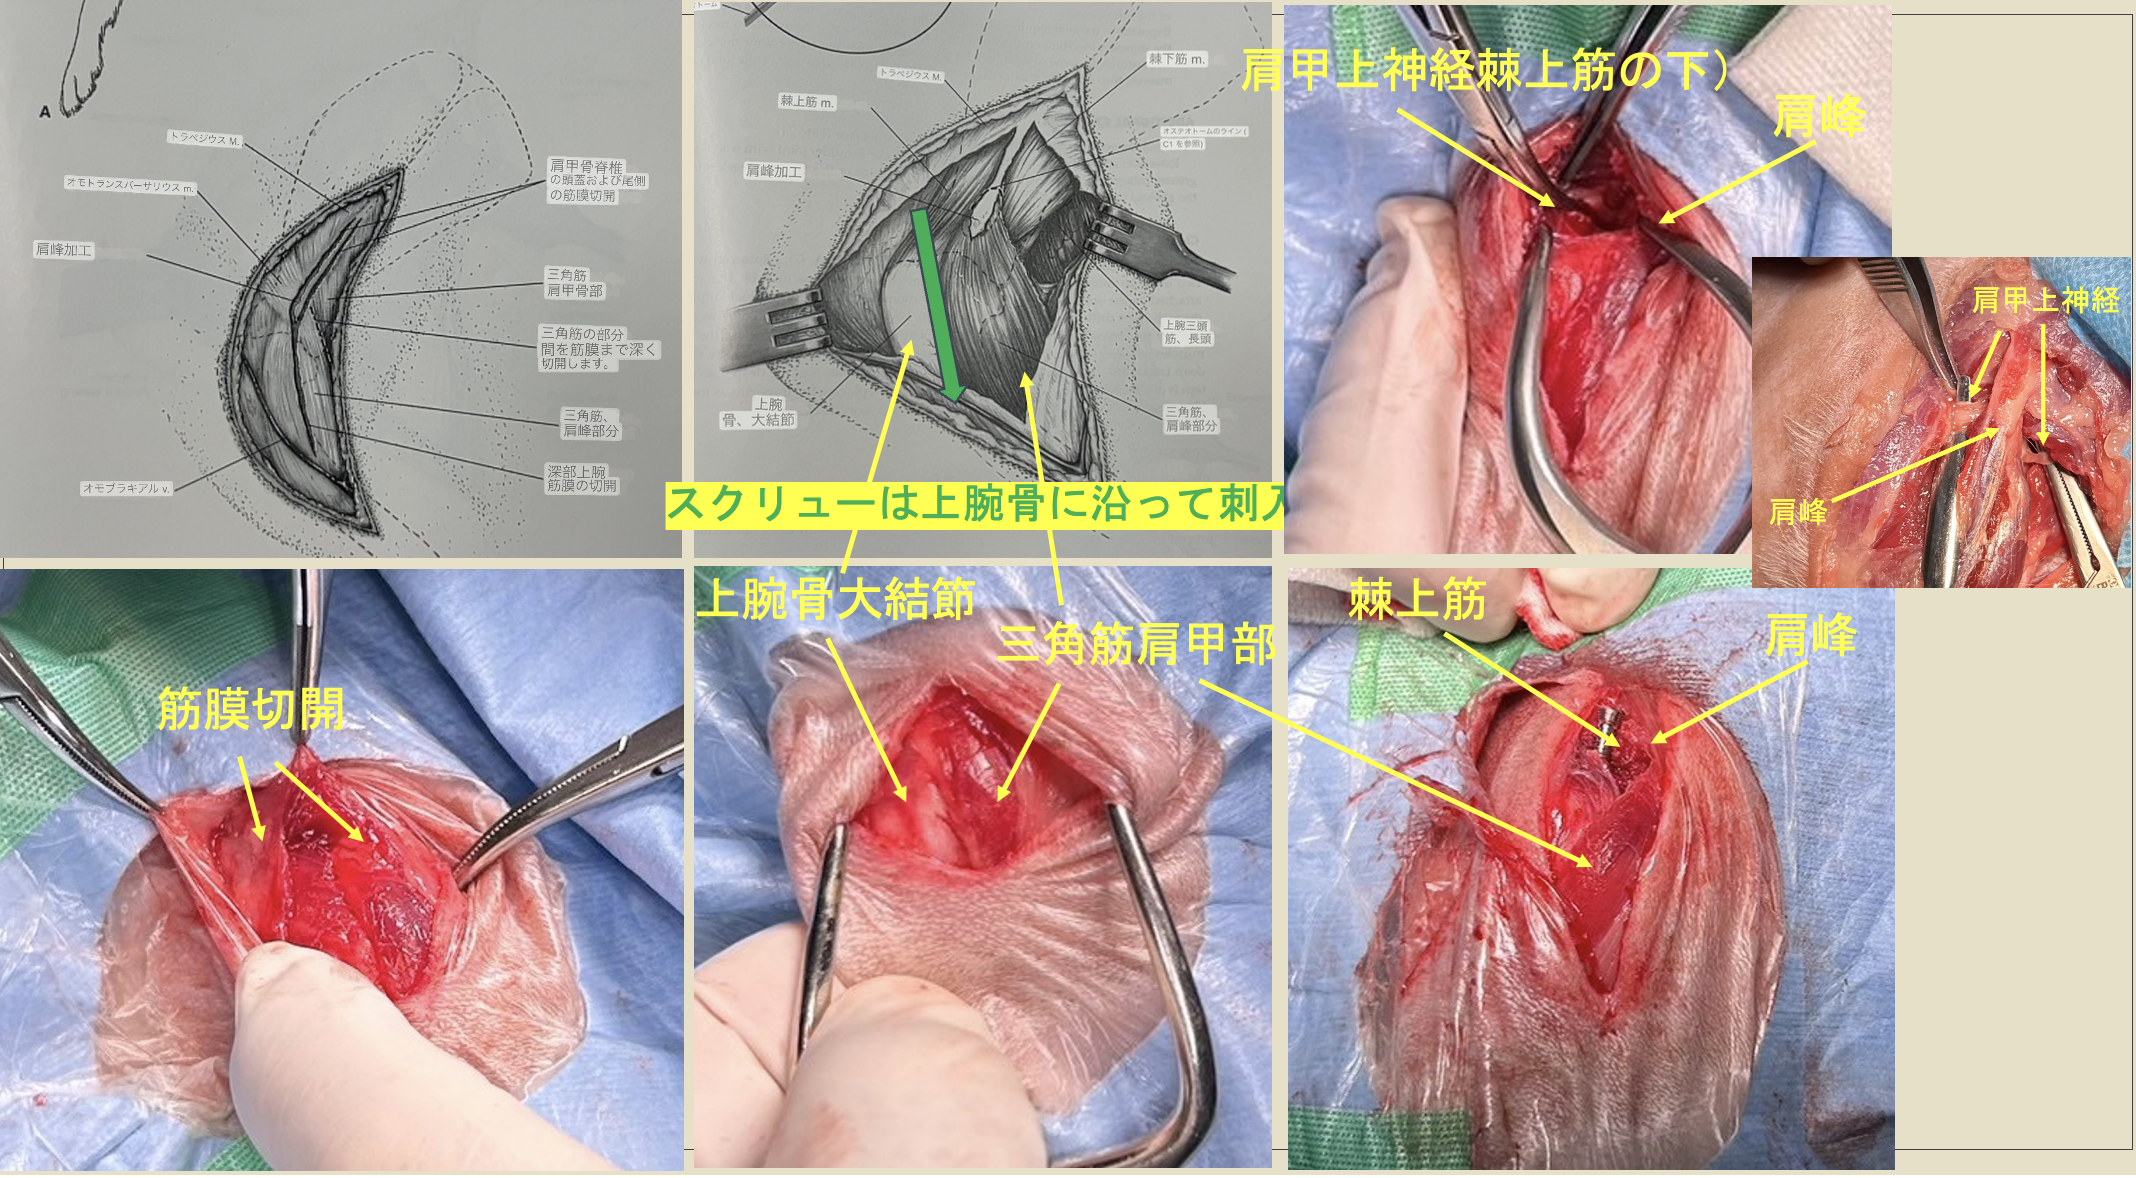

整形外科